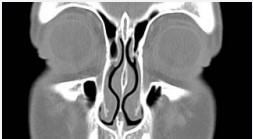

Radiologic imaging of the NSB has been reported using both CT and MR modalities (Figure 1).

Figure 1: Nasal Septal Swell Body* (NSB) as seen on coronal CT image.

The NSB is easily identified using either technique, and can also be shown to the patient during pre-op counseling.